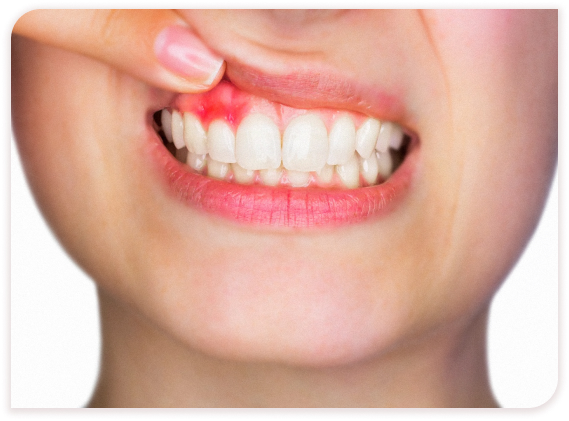

Кровоточивость дёсен и боль в них

Это признаки гингивита

Повод обратиться к пародонтологу:

Любые покраснения или посинения участков

слизистых оболочек

Рыхлость и кровоточивость десен